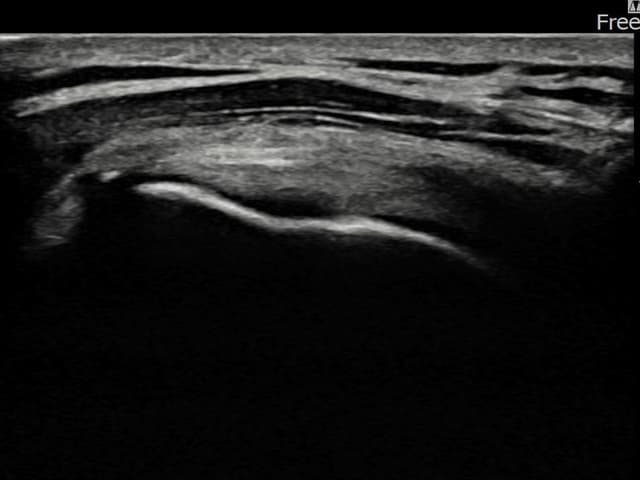

[経過期間: 23.08.16~23.10.18]

[縫縮術] 超音波検査にて右 棘上筋腱 関節面側部分断裂(7mm × 3mm (腱厚の約30%欠損))を確認。縫縮術施行後、腱の連続性が回復し、日常生活に復帰されました。